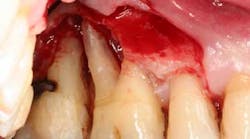

Figure 1: Full-mouth series taken in 2010, showing severe bone loss in the posterior maxillary molar and mandibular anterior incisor area.

At presentation, Martin was in his fifties with a medical history significant for controlled hypertension with no known food or drug allergies. He had been lackadaisical with his dental care in the past because of his busy schedule, but he was motivated to get his hygiene and treatment under control. He denied a history of smoking/alcohol/drug use. Based on his full-mouth series (figure 1) and clinical presentation, Martin had generalized, moderate bone loss with localized, severe bone loss in the posterior maxillary right and left quadrants (figures 2a and 2b) as well as the mandibular anterior incisor area (figure 3).